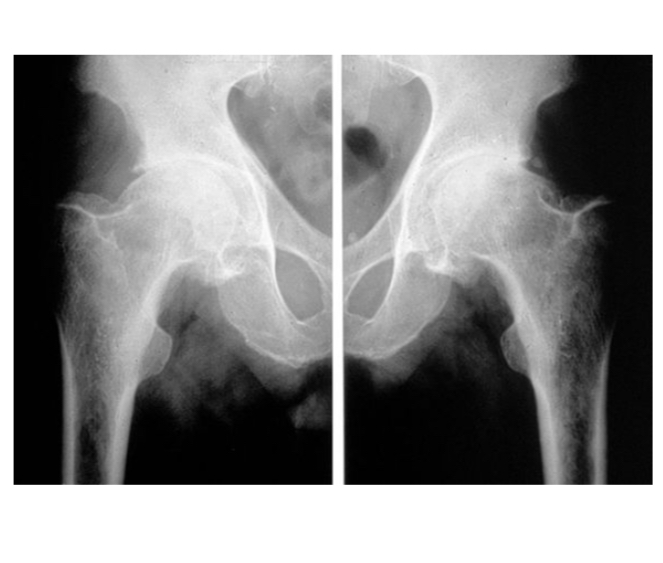

Coxarthrose bilatérale

pincement supéro-externe de l’interligne coxo-fémorale bilatérale

Coxarthrose destructrice rapide

pincement supéro-externe de l’interligne coxo-fémorale